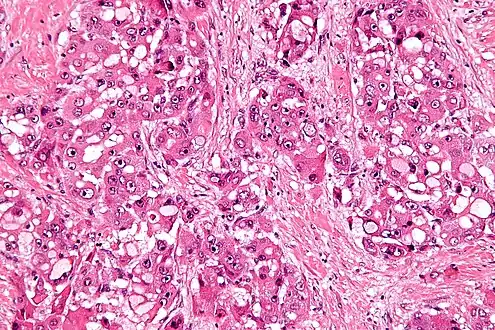

Micrograph of fibrolamellar hepatocarcinoma showing the characteristic laminated fibrosis between the tumor cells with a low NC ratio. H&E stain.

The histopathology of FLC is characterized by laminated fibrous layers, interspersed between the tumor cells. Cytologically, the tumor cells have a low nuclear to cytoplasmic ratio with abundant eosinophilic cytoplasm.[1] Tumors are non-encapsulated, but well circumscribed, when compared to conventional HCC (which typically has an invasive border).